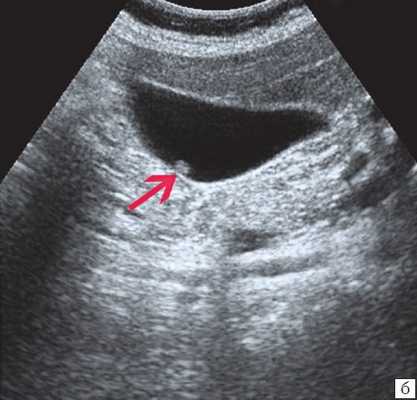

- Ультразвуковая диагностика. К визуализирующим методам диагностики холангита относятся УЗИ брюшной полости и печени, ультрасонография желчных путей. С их помощью удается получить изображение желчных протоков, выявить их расширение, определить наличие структурных и очаговых изменений в печени.

Инструментальная диагностика

В первую очередь пациентам с подозрением на холедохолитиаз проводят ультразвуковое исследование желчевыводящей системы, причём его используют на протяжении всего периода болезни, чтобы отследить динамику лечения. УЗИ помогает оценить состояние протока поджелудочной железы, показывает ворота печени и забрюшинное пространство. Иногда ультразвуковое исследование не позволяет рассмотреть камни в желчном протоке из-за вздутия кишечника, толстой передней брюшной стенки или скопления различных веществ в области ворот печени. Однако в 90 % случаев УЗИ справляется со своей задачей. В некоторых случаях УЗИ также помогает дифференцировать холедохолитиаз и опухоли в печени, желчном пузыре и протоках [7] [8] [9] .